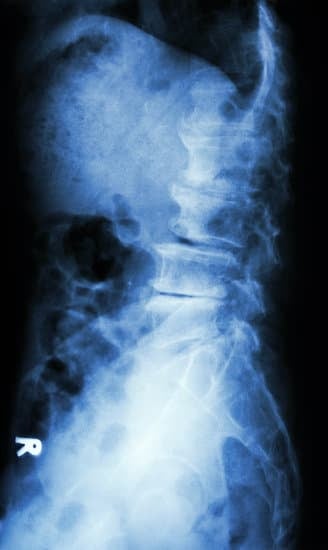

척추 전방전위증(Spondylolisthesis): 원인, 증상, 치료 및 예방법

✅ 척추 전방전위증(Spondylolisthesis)은 위쪽 척추뼈(추체)가 아래쪽 척추뼈보다 앞쪽으로 밀려나면서 신경을 압박하는 질환입니다.

✅ 주로 허리(요추)에서 발생하며, 허리 통증, 다리 저림(좌골신경통), 보행 장애 등의 증상을 유발할 수 있습니다.